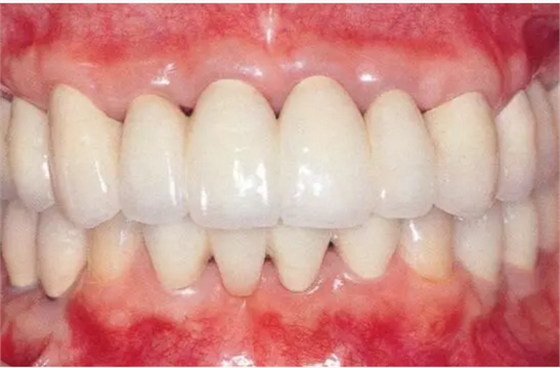

佩戴最終修復體時的正面照片。

▲圖19-14

佩戴最終修復體時的X光片。骨邊緣水平平坦,探診值維持在1~2mm。